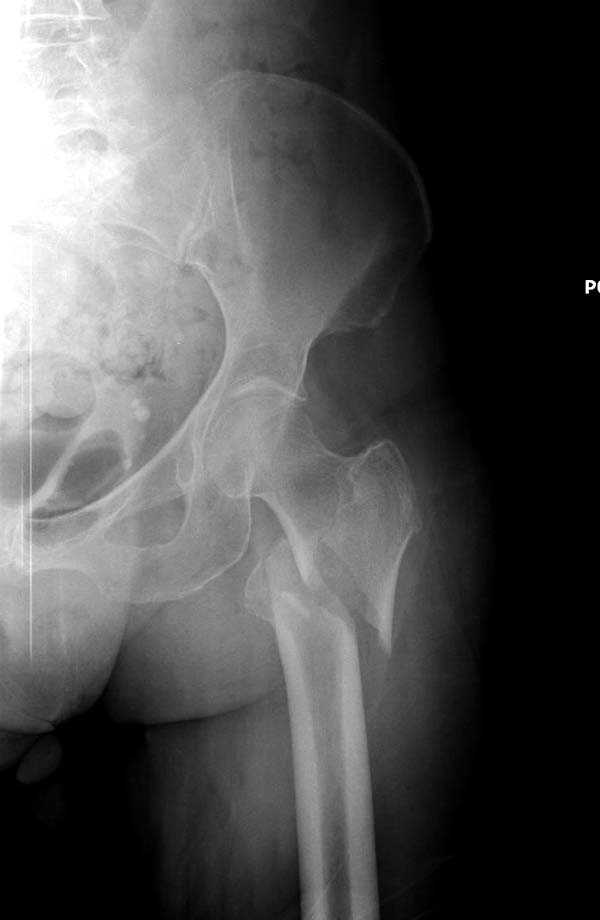

Здесь представлен случай, где в послеоперационном периоде обнаружена техническая ошибка, Gamma 3 установлен с нарушением методики. Больная в 91 лет, прооперирована через день после поступления и выписана через 48 часов.

При первом послеоперационном поликлиническом осмотре больная предъявила жалобы на боли в бедре. В серийных снимках обнаружен продольный перелом верхнего отдела бедра.

Мне тоже представляется, что это не единственная проблема. Продольные трещины заживают легко и быстро. Интересно, почему увеличился варус и

появилась медиализация дистального отломка.

Перелом А3, подвертельный, вероятно, на длинной версии гвоздя такого бы не произошло